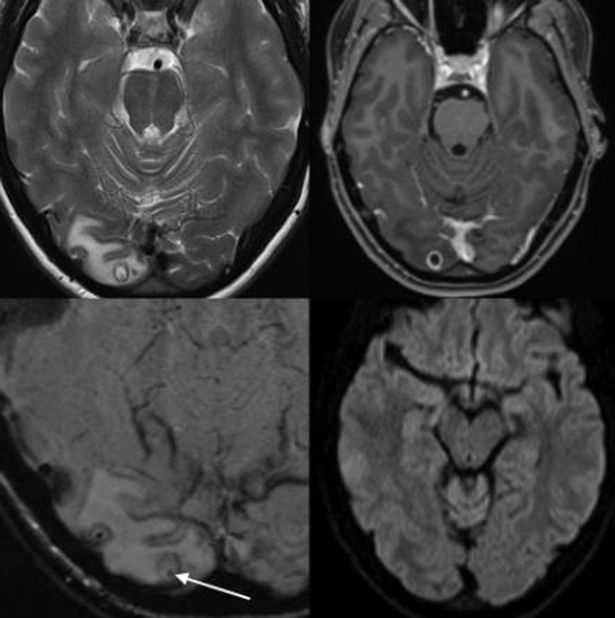

Αυτό που είδαν από την μαγνητική τομογραφία τους σόκαρε και για τον λόγο αυτό, αποφάσισαν να του προχωρήσουν άμεσα σε επέμβαση.

Ένα σκουλήκι-ταινία βρισκόταν στο κεφάλι της γυναίκας με αποτέλεσμα οι αφόρητοι πονοκέφαλοι της να μην γιατρεύονται με κανέναν τρόπο.